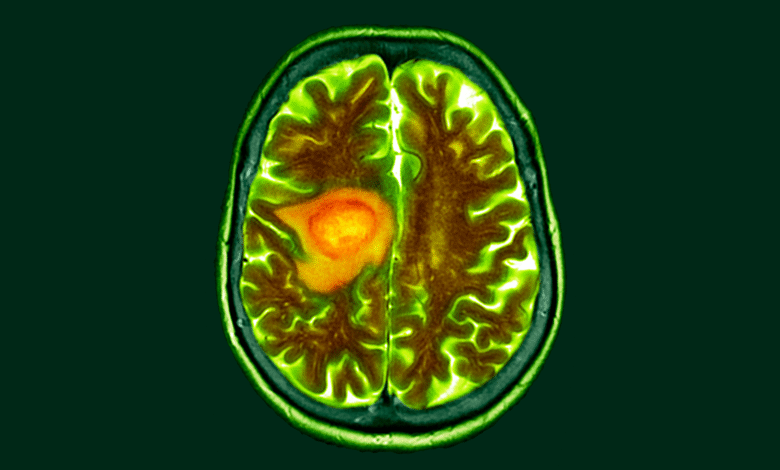

Změna stravy by mohla usnadnit léčbu rakoviny mozku, včasné studium náznaků

Nová studie naznačuje, že změna stravy může být náchylnější glioblastom s rakovinou mozku.

Práce, koordinovaná onkologem University of Michigan Volby Dr. Danposoudil, jak glioblastom deformuje jeho metabolismus v lidských i zvířecích mozcích. Studie ambiciózně kombinovala laboratorní výzkum a klinickou praxi tím, že některé z jejích dat z tkáně odebraných z mozků pacientů podstupujících chirurgii rakoviny podstupuje. Studie vyžadovala spolupráci odborníků na chirurgii mozku lidských a hlodavců, metabolických drah a molekulární analýzy.